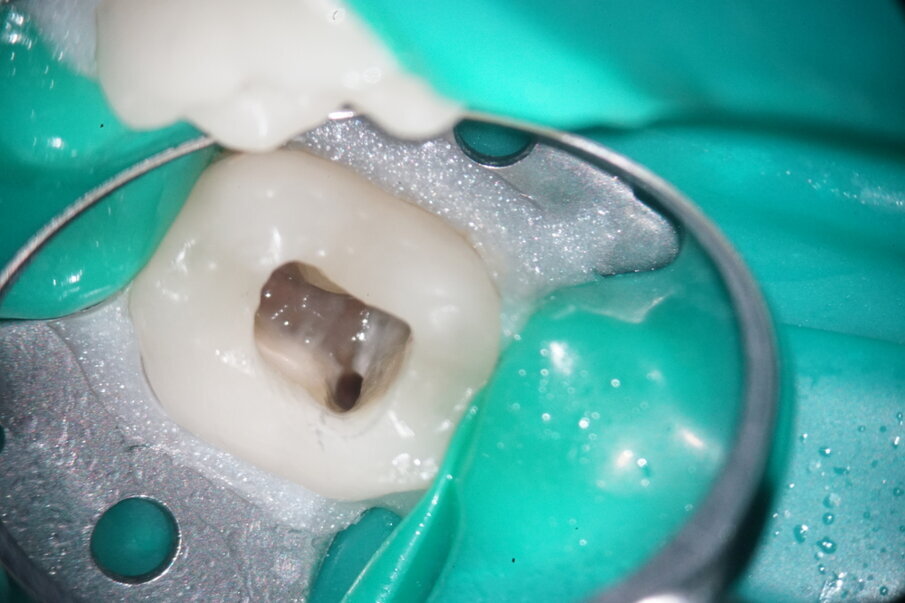

After applying the dental dam and preparing the access cavity, the next step was to remove the existing obturation material (Figs. 3 & 4). A high-speed rotary HyFlex Remover was used for this purpose (Fig. 5). The revision file efficiently removed the materials from the root canal so that additional solvent could be dispensed with during treatment. Unlike in other cases, the plastic carriers in this case were not extracted with an aid, but were machined (see video above). The non-cutting tip of the retreatment file protects the surrounding tooth structure during this procedure, which makes handling even easier.

Fig. 3: Initial situation of mesial canals.